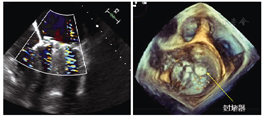

2019年9月10日,手术在介入手术室进行,患者取仰卧位,全身麻醉后行气管插管机械辅助通气,同时经食管超声心动图辅助术中影像学评估及全程监测心包及胸腔。术前经胸超声心动图提示:心包粘连,心动周期内左心室前壁、心尖处与胸廓位置相对固定。穿刺右侧股动脉置入6F短鞘,泥鳅导丝引导4.0左冠状动脉导管逆行至左冠状动脉开口,分别在前后位、左前斜45°、右前斜38°、足位26°进行左冠状动脉选择性造影,明确心尖无冠状动脉血管区域,同时借助X线下直头镊辅助定位,最终确定经皮穿刺进针点为左侧腋前线第5肋间(图2)。行经皮心尖穿刺,置入5F短鞘,鞘管头部放置于左心室中间。调整C臂至右前斜38°、足位26°使二尖瓣机械瓣为一个平面且左心房、左心室展开,经短鞘送入5F猪尾导管行左心室造影,提示:二尖瓣机械瓣瓣周漏,心脏收缩期反流血液迅速充盈左心房。随后,撤出5F猪尾导管,使用2.6米直头泥鳅导丝引导5F单弯导管进入左心室内,探过瓣周漏口进入左心房使单弯导管盘成圈,撤出泥鳅导丝置换为预弯头部的Amplatzer Ultrastiff加硬导丝进入左心房内打圈。撤出单弯导管及短鞘,沿加硬导丝送入COOK 5F 90 cm外周长鞘跨过瓣周漏口进入左心房,撤出加硬导丝。结合术前影像学测量,选择6 mm ADO-Ⅱ封堵器送入,X线下精准定位于瓣周漏口并展开。推拉试验证明封堵器定位牢固,X线下显示无卡瓣现象。遂释放封堵器,置换猪尾导管行术后左心室造影,结果提示:封堵器位置良好,瓣周反流消失。经食管超声心动图同样证实封堵器位置良好,二尖瓣机械瓣叶活动良好,瓣周反流消失。经外周长鞘送入第2枚6 mm ADO-Ⅱ封堵器,回撤长鞘时将封堵器紧贴左心室壁释放封堵穿刺针道,X线及超声心动图双重明确封堵器一端紧贴于心室游离壁,一端于心肌外,遂释放封堵器。术后经食管超声心动图证实无心包积液,胸腔积液。术后即刻,患者苏醒并撤除呼吸机,转至心脏重症监护室观察。3天后,复查超声心动图提示瓣周反流消失、心包、胸腔无积液,患者平稳出院。

术后3个月随访,超声心动图提示二尖瓣机械瓣瓣周无反流,封堵器位置良好,二尖瓣、主动脉瓣机械瓣瓣叶活动良好;心尖穿刺处封堵器位置良好,各心室壁搏幅正常。提示经心尖穿刺封堵瓣周漏效果良好,穿刺针道预后佳,室壁运动未受影响。